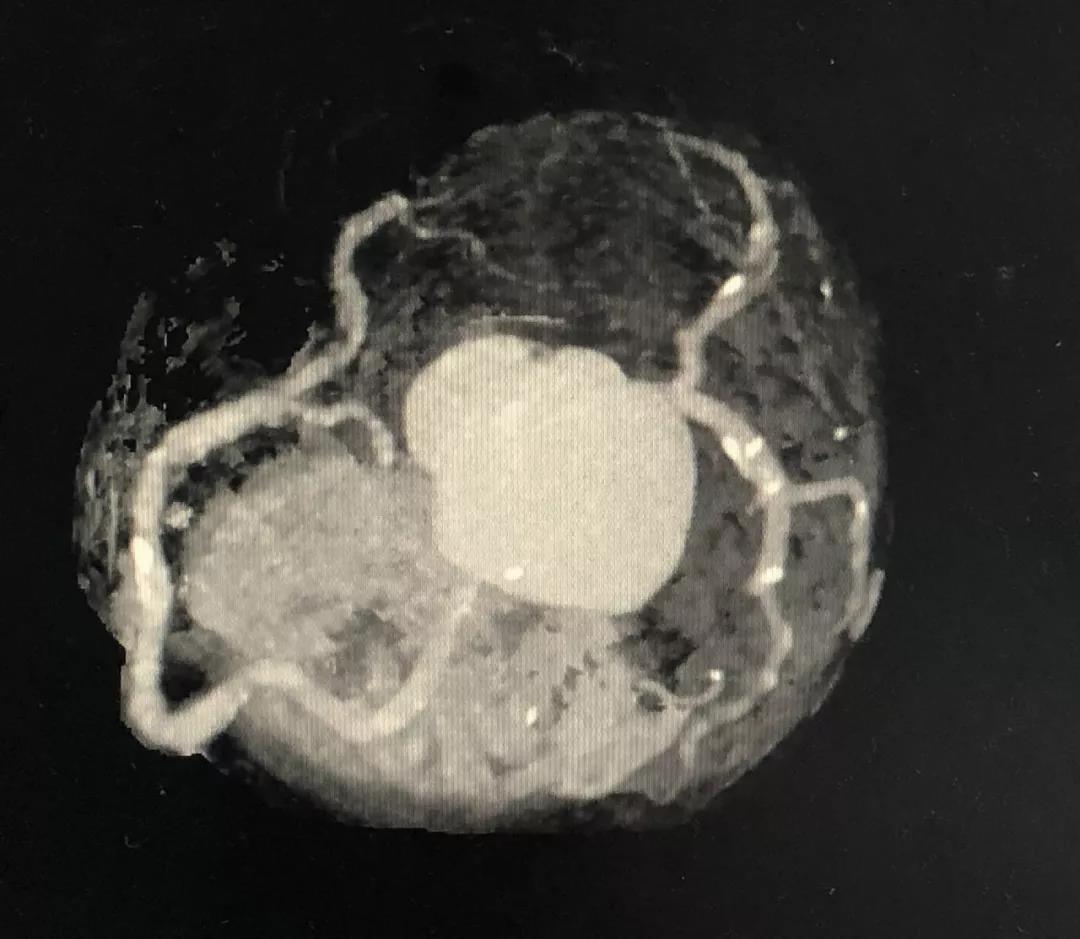

冠状动脉CTA

CCTA LAD病变特点:

近段血管较直

中远段血管偏细

中远段血管病变弥漫

病变段扭曲不很明显

病变段无重要分支发出

病变血管段有局灶点状钙化

CCTA LCX病变特点:

LM前分叉正常

LCX相对较直

中段病变伴局灶点状钙化

5、左主干无钙化,前分叉正常,为选用7F指引导管和/或使用延长导管提供了机会。